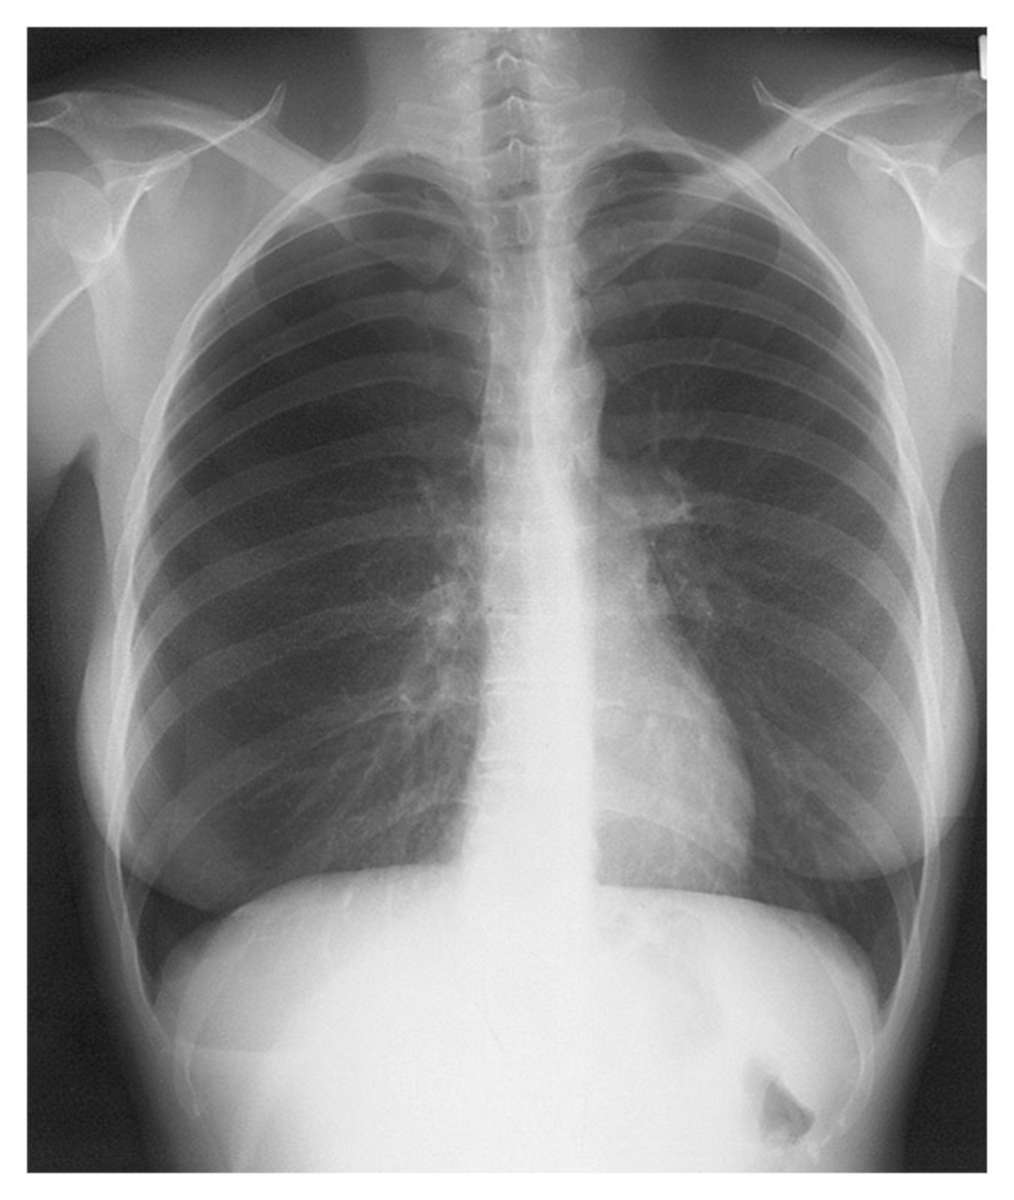

Woman with Recurrent Right-Sided Chest Pain Synchronously with her Menses Post category:Spot Diagnosis Post published:November 8, 2021 Share on Facebook Share on X (Twitter) Share on Pinterest Share on Email Share on Reddit Woman with Recurrent Right-Sided Chest Pain Synchronously with her Menses This 38-year-old woman developed recurrent right-sided chest pain synchronously with her menses. What is the most likely diagnosis? CLICK HERE FOR FULL CASE AND ANSWER Share on Facebook Share on X (Twitter) Share on Pinterest Share on Email Share on Reddit Read more articles Previous PostNonpruritic, Well-Circumscribed, Scale-Covered, Erythematous Plaques on Palms and Soles Next PostVarices of the Chest and Abdominal Wall You Might Also Like Palpable, Ropelike Cord from the Left Medial Malleolus to the Groin July 7, 2021 67-year-old Woman with a 6-month History of Dyspnea and Dysphagia December 2, 2021 Patient with Diabetic Nephropathy and Secondary Hyperparathyroidism May 11, 2022